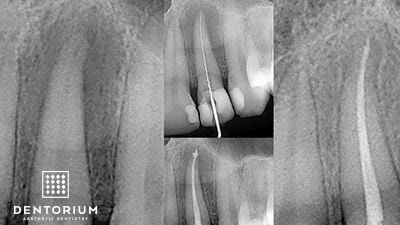

Immediamente dopo il trattameneto si procede con RVG controllo del canale trattato.